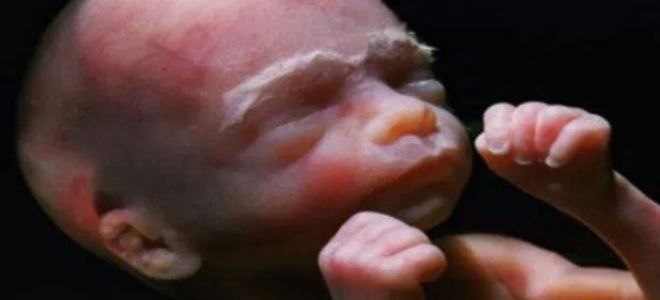

22 недели беременности – как выглядит ребенок?

На 22-й неделе беременности внешний вид малыша напоминает маленького человека. На его лице начинают формироваться брови и ресницы, а на пальцах рук и ног появляются крошечные ноготки. Костная ткань становится более прочной, а позвоночник стремительно растет в длину. На поверхности кожи можно заметить множество тонких и коротких волосков, известных как лануго.

В области плечевого пояса появляется сероватое вещество, напоминающее жир. Это первородная смазка, которая со временем будет все больше покрывать тело ребенка. Ее основная функция заключается в облегчении прохождения плода через родовые пути во время родов. Кожные покровы при этом сохраняют красноватый оттенок.

На 22 неделе беременности плод продолжает активно развиваться. По мнению экспертов, в этот период его длина достигает примерно 28 сантиметров, а вес составляет около 500 граммов. Кожа малыша становится менее прозрачной, а под ней начинает формироваться жировая прослойка, что придаёт ему более округлые формы. Внутренние органы продолжают совершенствоваться: легкие готовятся к первому вдоху, а печень активно производит желчь.

На 22-й неделе беременности происходит множество изменений в развитии малыша, которые врачи описывают как значительное преображение. В этот период активно формируется подкожно-жировая клетчатка, благодаря чему тело плода приобретает более округлую форму, а кожные складки становятся менее заметными. Ребенок начинает выглядеть более пухлым, на его голове появляются первые волоски. Эти волоски играют важную роль, удерживая первородную смазку, которая со временем покрывает тело малыша. Эта смазка защищает его от неблагоприятных факторов, питает кожу и облегчает процесс прохождения через родовые пути во время родов.